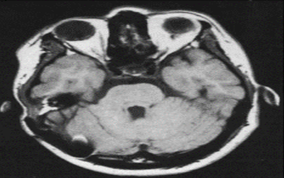

Imaging with magnetic resonance (MRI) is a non-invasive method that uses magnetic field to generate radiofrequency (RF) field to produced images of soft tissue with high resolution. It was described in 1930s and 40s. the principle of MRI is based on the interactions of protons (hydrogen atoms), strong magnetic fields and radiofrequencies of different energies. (Figure 7).19

Figure 7 MRI brain scan.20

Patients is placed inside the strong magnet at still position to reduce motion artefacts in the image. MRI produced detailed anatomical structure of the brain,20 spinal cord and other body parts, it has the advantage of being able to visualized anatomical images in three planes: axial, sagittal and coronal views.21 MRI has the advantages of giving higher soft tissue contrast and being able to detect blood flows and cryptic vascular malfunctions, MRI has the advantage of being free from ionizing radiation exposure over computed tomography (CT) and conventional x-ray machines. T1-weighted, T2-weighted, diffusion weighted imaging (DWI), Proton density (PD-weighted), Fluid attenuated inversion recovery (FLAIR), Auto-calibrating reconstruction for cartesian imaging (ARC), and Generalized Auto-calibrating partial parallel acquisition (GRAPPA) are the imaging sequences used in magnetic resonance imaging (MRI). ARC is multi-coil parallel imaging (PI). Based on the time to echo (TE) and repetition time (TR), T1-weighted and T2-weighted are generated. T1-weighted has longer TE and TR. Another difference is by looking at cerebrospinal fluid (CSF), CSF is darker in T1-weighted and bright in T2-weighted images. The FLAIR sequence is mainly T2-weighted image with longer TE and TR. Diffusion weighted image is used to detect random movement of water proton. Proton density is in between T1 and T2 with pulse sequence of long TR and short TE.21 MRI is broadly classified into structural magnetic resonance imaging (sMRI) and functional magnetic resonance imaging (fMRI), sMRI is mostly applicable to clinical practices and research purposes. The distinction between sMRI and fMRI is difficult to make as function and structure are closely related, from biological view point fMRI provides dynamic physiological information which includes blood oxygen level depended (BOLD), perfusion and blood flow, while, sMRI displays static anatomical information which include studies of epilepsy, schizophrenia, dementia, trauma, tumours and multiple sclerosis.22 Structural MRI sequence has high contrast between gray matter and white matter giving room for volume quantification of the gray and white matter. The common method used for processing sMRI is voxel-based morphometry, it can also be used to assess the degree of cortical folding or pattern and variation of cortical gyrification. sMRI has the advantages of clear interpretation, early implemented across centres and relatively low cost over fMRI, electroencephalography and proton magnetic resonance spectroscopy23 (Figure 8).